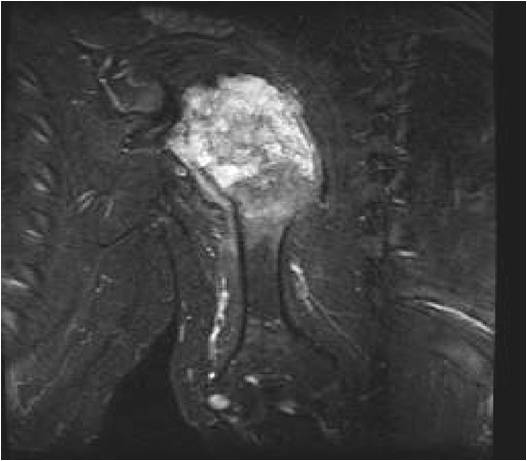

MRI:

- Lobulated margin (Lobular Growth Pattern)

- T1 Weighted Images: Intermediate Signal Intensity

- Calcifications will be low signal

- T2 Weighted Images: High Signal Intensity

- High water content shows as high signal on T2 weighted images

- Marked increased intensity long TR images

- Calcified chondroid – low intensity all sequences

- There should never be any cortical destruction nor a soft tissue component. If this exists then the tumor must be a chondrosarcoma.

- Endosteal scalloping and cortical expansion is acceptable for phalangeal tumors. In most benign long bone cartilage tumors there is minimal endosteal scalloping but there should be no cortical expansion nor thickening. There should be no cortical destruction and no soft tissue component associated with an enchondroma. Cortical destruction, periosteal thickening, cortical expansion and a soft tissue component indicates a chondrosarcoma of the long bone.